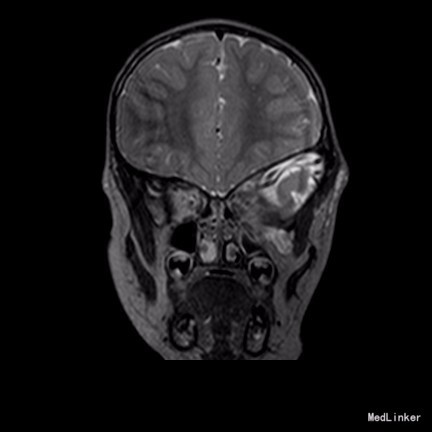

2岁9月患儿,因“左眼睑下垂1年余,头痛、呕吐8天”入院。家属1年前发现患儿左侧眼睑下垂,无法自行张开,一直未予特殊诊治。8天前患者哭闹频繁,诉头痛如爆炸样,剧烈难忍,并出现呕吐胃内容物数次,无伴抽搐、视力下降,无意识障碍。当地医院头颅MRI提示:左侧眼眶扩大,左侧眼球外上方泪腺区见一条状迂曲异常信号影,T1WI呈等信号,T2WI上病灶外缘呈高信号,内为等信号,增强扫描病灶中央呈条状明显强化影,边缘无明显强化,双侧大脑半球对称,灰白质对比正常,未见局灶性信号异常,左侧中颅窝前分蛛网膜下腔增宽,内为脑脊液信号;各脑室、脑池大小、形态均正常,中线结构居中,幕下小脑、脑干无异常,矢状面示垂体大小形态正常,未见局灶性信号异常;增强扫描未见明显异常强化。

患儿术后2周左眼睑下垂较术前好转。双侧瞳孔反射、眼球活动均无异常。 丛状神经纤维瘤主要发生于眼睑,在出生后或幼年时期即出现症状和体征。侵袭范围广泛,包括眼睑、眶内软组织、眶骨和邻近的脑、颞部等。眼部最早和最多见为上、下睑软性肥厚,皮下瘤组织增生,使上、下睑隆起。眼睑皮肤常有淡棕色色素斑,眼球向前突出和向下移位。眼球突出虽然很显著,但向眶内纳入并不困难。肿瘤组织可直接侵袭眶内各种结构,上睑提肌首先被波及,引起上睑下垂,上举不足或不能。MRI可准确显示病变的范围尤其显示病变与邻近结构的关系,也可清楚显示其他部位伴发的肿瘤,但难以清晰显示眶壁骨质改变。手术治疗是必要的,手术切除应注意以下问题:1.眼睑病变的切除;2.眶内病变的处理;3.提上睑肌的处理;4.眶骨缺失的处理。丛状型术前诊断容易,但治疗较为棘手,易复发。